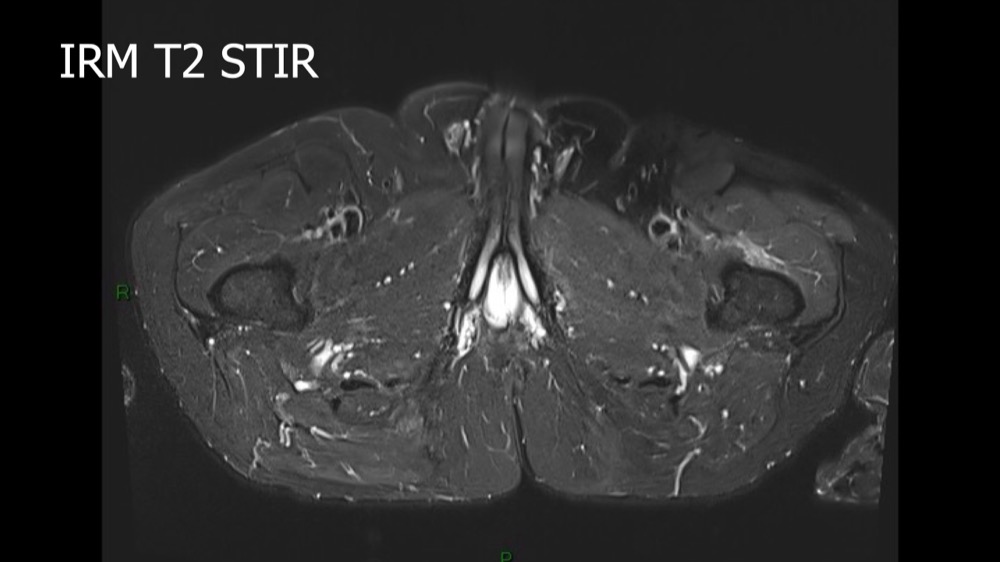

Lombo-cruralgie subaiguë trompeuse

Pascalie Jallerat 22/06/2020